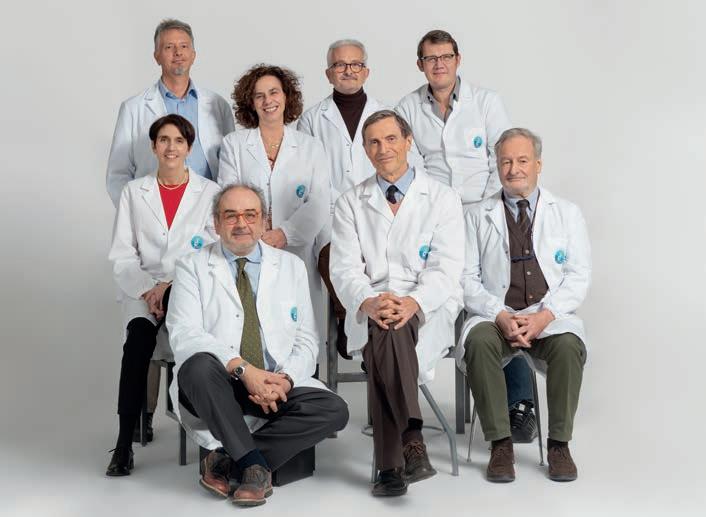

Fare ricerca significa anche scambio, dialogo, condivisione. “Altrimenti è come se la mano destra non sapesse cosa fa la sinistra” spiega il direttore scientifico di AIRC Federico Caligaris Cappio al convegno CrossFertilization, cioè fertilizzazione trasversale. L’evento ha riunito, per la prima volta, i responsabili e i ricercatori degli 8 programmi speciali AIRC per lo studio delle metastasi, finanziati grazie ai contributi del 5 per mille e coordinati da Alberto Bardelli, Maria Chiara Bonini, Robin Foà, Michele Maio, Alberto Mantovani, Stefano Piccolo, Maria Rescigno e Alessandro Maria Vannucchi. Tenutosi a gennaio 2023 presso la sede di IFOM, l’Istituto di oncologia molecolare di AIRC, l’incontro è stato organizzato per permettere agli scienziati di confrontarsi sui propri risultati e discutere le prospettive future dei loro progetti. In questo articolo, per motivi di spazio, presentiamo a titolo esemplificativo solo alcuni dei lavori presentati durante l’evento. Maggiori informazioni sono disponibili sul sito programmi5permille.airc.it.

I responsabili degli 8 programmi 5 per mille AIRC per lo studio delle metastasi